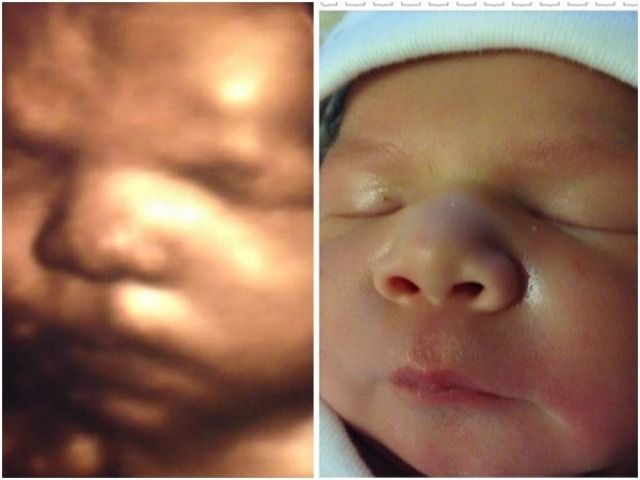

Our 4D/HD ultrasounds can begin as early as 7 weeks, giving you a clear and awe-inspiring first look at your baby. And it’s never too late—we’re experienced in scanning up to 42 weeks into pregnancy.

Every ultrasound—even 4D/HD—begins with a 2D scan, also known as grayscale. These are the classic black-and-white images you're used to seeing. This foundational imaging technique reveals a wealth of information, and we’re excited to share that with you.

Our 2D Connection session provides essential information and, most importantly, a beautiful opportunity to begin bonding with your baby. From there, you can personalize your experience by adding 4D/HD imaging and selecting from a variety of thoughtful extras to create the perfect package for you.